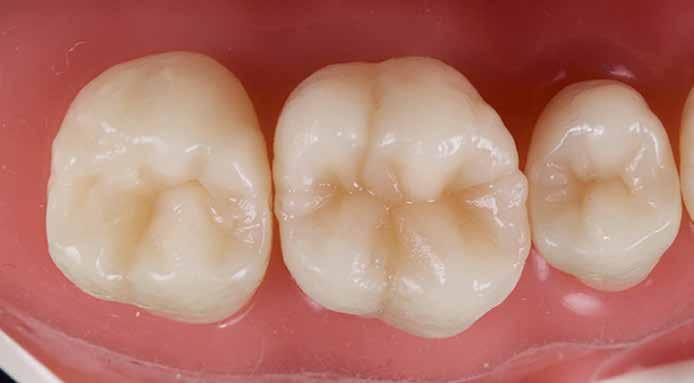

A restauráció polírozását korongok és szilikonpolírozók kombinációjával végezte, majd az okklúzió ellenőrzését követően a pácienst a rendelőből otthonába bocsátották. Megjegyzendő, hogy a finírozást követően az eredeti okkluzális anatómia csak minimális mértékben módosult (17. ábra).

2. eset

Egy 26 éves páciens a jobb felső első molárisának ideiglenes, endodonciai kezelést követő, I. osztályú restaurációjával jelentkezett. Mivel a fogban jelentős mennyiségű dentin és zománc volt jelen, valamint a marginális peremek épek voltak, a páciens tájékoztatása és beleegyezése után a kezelési terv a direkt kompozit restauráció volt (18. ábra). A fog preparálása az 1. esetben leírtak szerint történt (19. ábra).

Végül a szerző az üreget a „Modified Super-Closed Sandwich Approach” [20] technikával állította helyre (amely a klasszikus rezin-módosított üvegionomer zárt-szendvics technika módosított változata), és az okkluzális iránytű módszerét alkalmazta a rágófelszín lezárására (20. ábra).

Jelen publikáció egy egyszerű, könnyen elsajátítható, mégis kiszámítható technikát kíván megosztani, amely lehetővé teszi minden fogorvos számára, hogy gyönyörű, élethű, esztétikus restaurációkat készítsen, amelyek nem csak funkcionálisak, hanem rétegezést követően nem, vagy csak minimális rágófelszíni korrekciót igényelnek. Mindez megvalósítható egy klinikailag reális időkereten belül egy átlagos fogászati rendelőben, minimális számú kompozit árnyalat és minimális számú eszköz birtokában, valamint az „okklúziós iránytű” ismeretének segítségével.